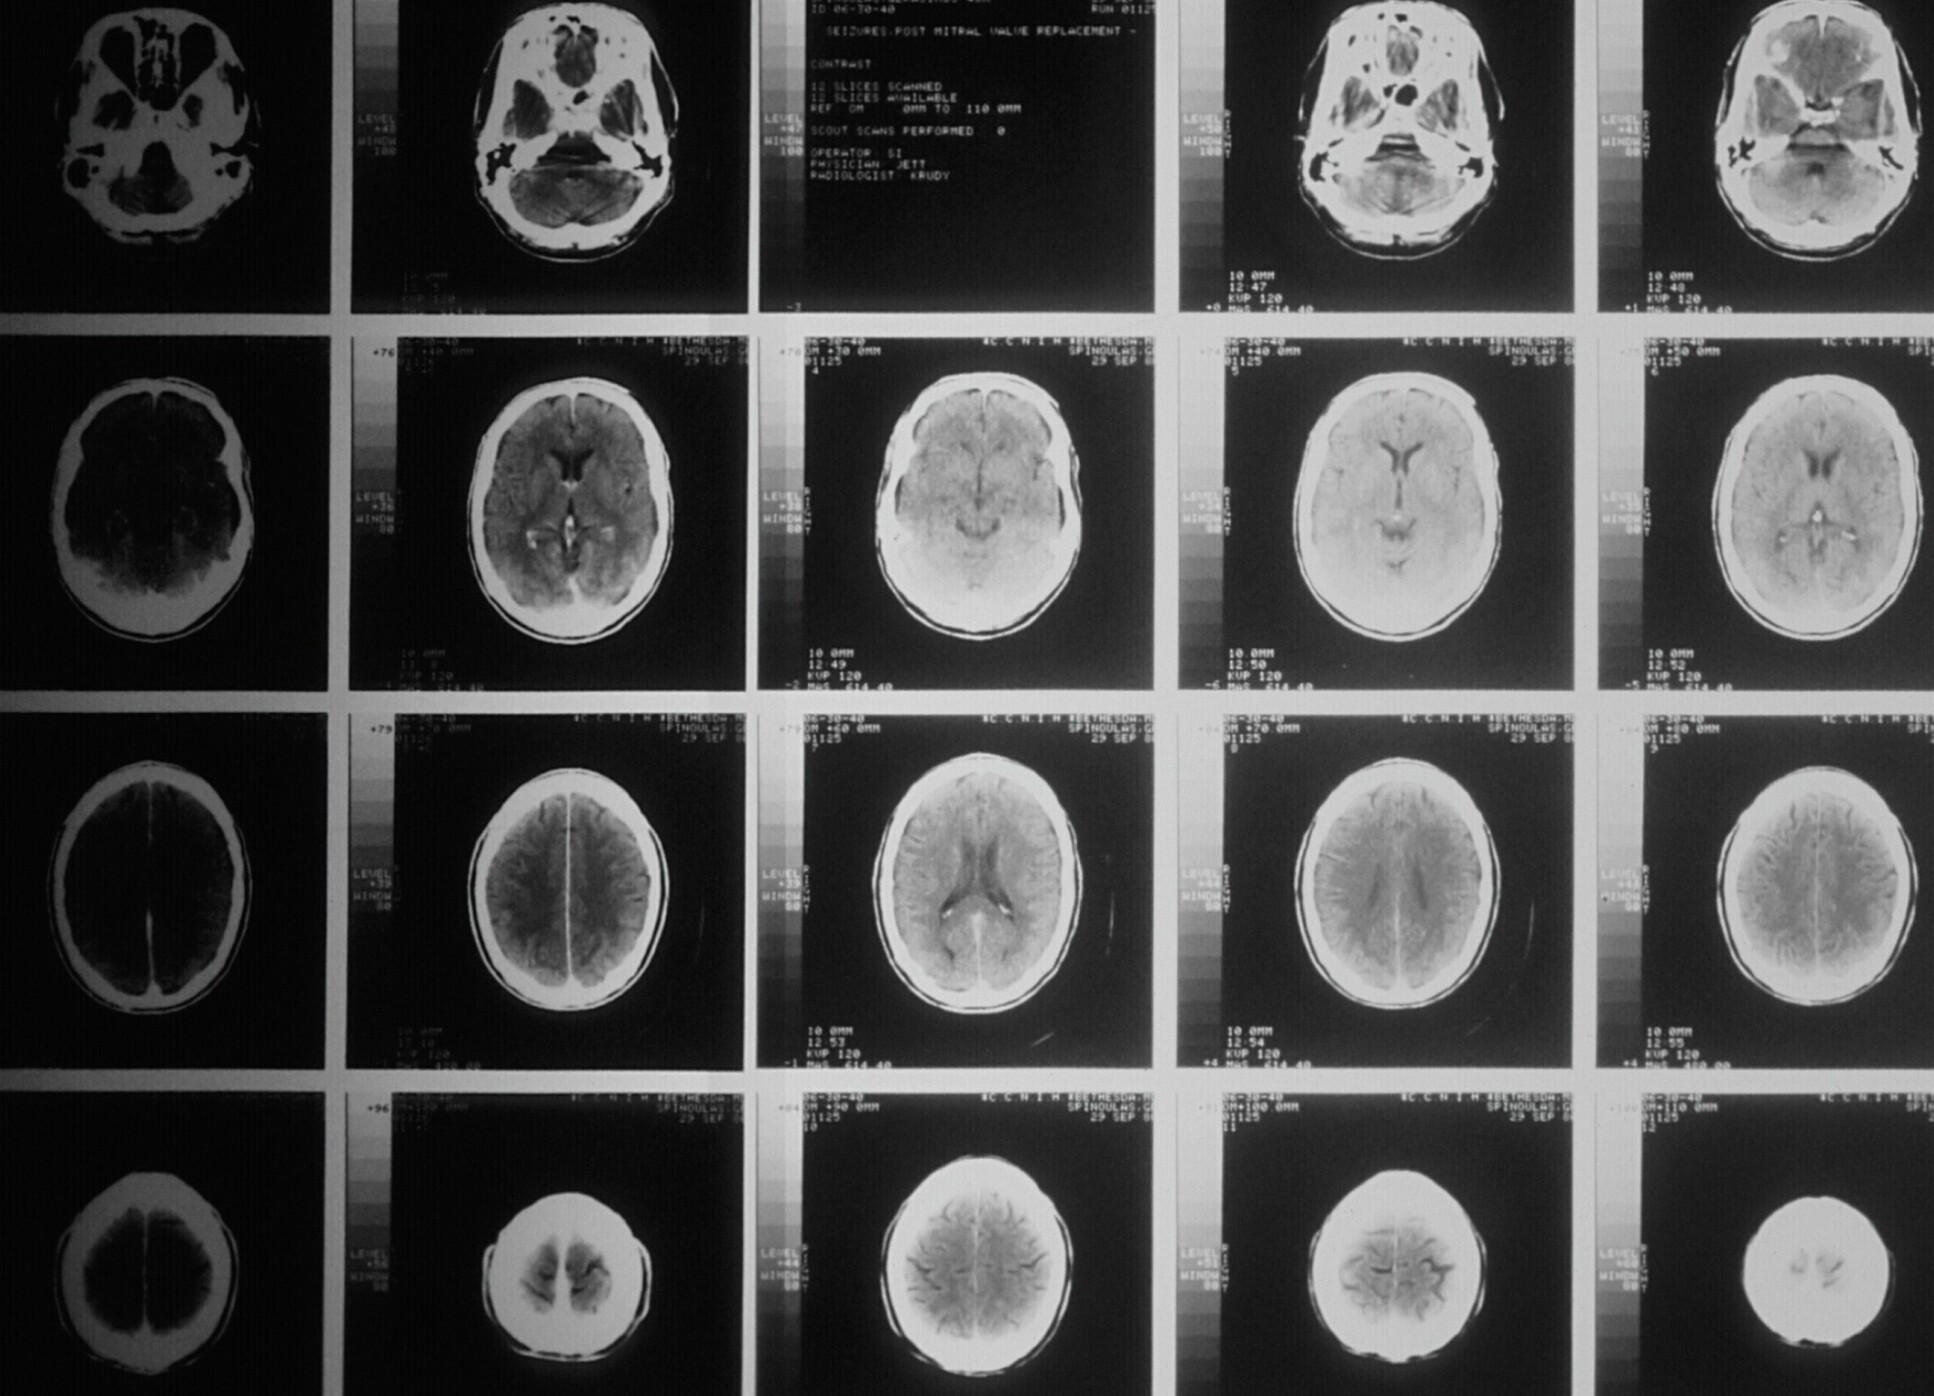

Brain scan

The project will bring together a mix of world-class research, clinical practice, diagnostics, advanced analytics and data platform capabilities.

Imperial researchers are part of a European consortium aiming to transform the healthcare approach to Alzheimer's disease.

The project, AD-RIDDLE, will offer healthcare providers with resources and interventions to help detect, diagnose, prevent and treat Alzheimer’s disease.

Funded by the Innovative Health Initiative – an EU public-private partnership funding health research and innovation – the consortium of 24 partners unites academic and industry partners, healthcare providers, regulatory bodies, and patient organisations, bringing together a mix of world-class research, clinical practice, diagnostics, advanced analytics and data platform capabilities to the project.

Professor Lefkos Middleton, from the School of Public Health, said: “Our Ageing Epidemiology Research Unit, part of the School of Public Health and the Primary and Public Health Directorate of Imperial College NHS Healthcare Trust will actively contribute across all AD-RIDDLE worksteams, whose success will have a direct positive impact on early and accurate diagnosis of our own patients and across Europe.”